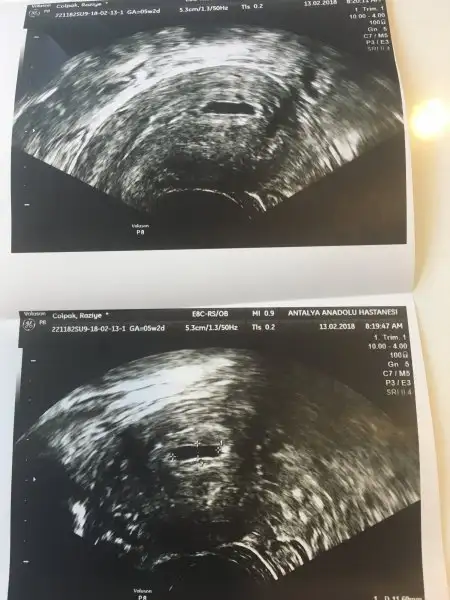

merhaba kızlar kafama birşey takıldı.

5.haftada kesesi vajinal yoldan gördü doktor henüz içinde bebeği göremedik ama yolksac oluşuyor dedi onu gördü.

internette biryerde rast geldim kesenin şekli kalemle çizilmiş gibi yuvarlar olmalıymış eger girinti çıkıntı varssa kese basıncı ve sıvısı yetersiz olabiliyormuş. benim kesemde de var sanki girinti çıkıntı sizce böyle şeyler normal mi sorun yaşayabilir miyim. bilen varmı bı yorum yapsanız